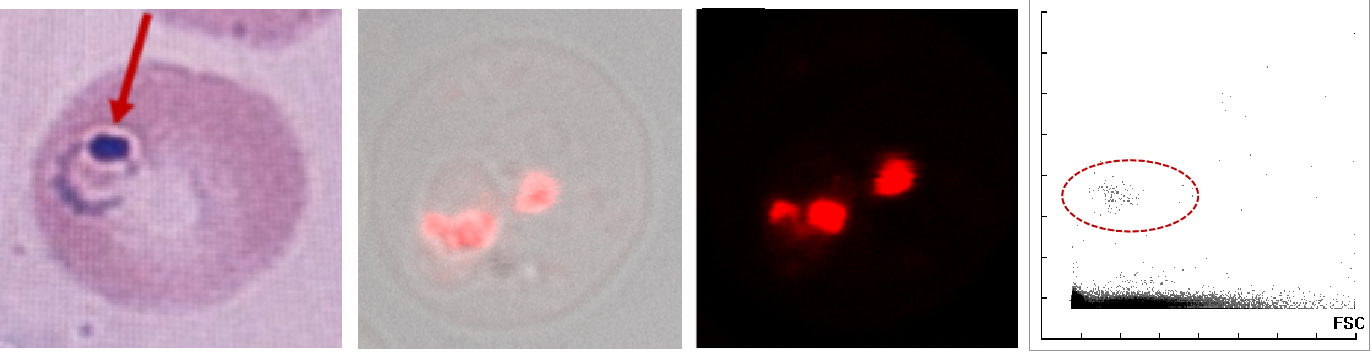

基于深度学习的外周血异常红细胞形态识别模型的建立及验证

本研究收集了三家医院的1800例红细胞异常样本,使用SC-120和MC-80进行推片染色以及图像采集后,分别从细胞和样本维度对红细胞异常类型进行标注,其中细胞维度从红细胞形状/内含物/血红蛋白含量异常进行标注,样本维度则标注红细胞分布与排列异常,采用数据扩增、焦点损失和标签平滑等技术解决数据类别不平衡和和部分异常红细胞易混淆等标记难题后,构建单阶段目标检测网络识别各类型异常红细胞并增加传统分类规则对部分类型进行修正。该模型在验证集中识别各种异常红细胞类型的准确率在 86.18% 到 99.74%之间;对红细胞碎片和疟原虫检测的准确率分别为97.58% 和 97.12%。本模型为红细胞分类提供了一种简单而高效的方法,可以大大提高异常红细胞识别的效率及准确率。

6

合作医院:¹中山大学附属第一医院  ²上海交通大学医学院附属瑞金医院  ³云南省寄生虫病防治所

作者:赵滨 张静娴 李俊勋¹ 蔡褀² 刘慧³ 张帆¹ 刘妍 叶波